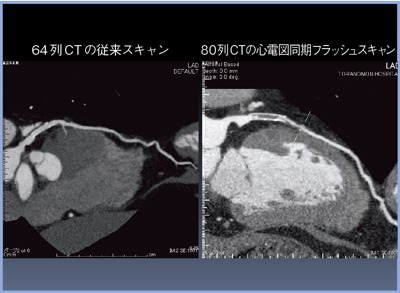

当院では,2011年3月に,80列CT「Aquilion PRIME」を導入。以後,心大血管領域のCT検査は,すべてAquilion PRIMEで行っている。臨床の一例を(図1)に示す。

冠動脈CTの撮影加算を請求するためには,64列以上のマルチスライス型CTを有し,画像診断管理加算2の施設基準を満たしていることが条件となる。今回,実際に80列CTを使用してみると,従来の64列CTとは格段の差があることがわかり,導入のメリットを実感している。本講演では,導入後1年余りの使用経験から,循環器領域における有用性について報告する。

図1 労作性狭心症 RCA #2狭窄

心電図同期フラッシュスキャンは,高速ヘリカルピッチを用い,至適心位相,すなわち拡張中期にのみX線を曝射する撮影方法である。従来の64列CTにおける,広い範囲にオーバーラップしてX線をかけながら,低ヘリカルピッチで撮影する心電図同期法に比べると,約70%の被ばく低減を実現することができる(図2)。

図2 心電図同期フラッシュスキャン

また,撮影に必要な心拍数を3〜5心拍に減らせるため,心臓の動きによって積算していく“ぶれ”も,心拍数が減ることで低減される。

正常冠動脈を心電図同期フラッシュスキャンにより5心拍5秒で撮影した(図3)。ボリュームレンダリング画像(a)はもちろん,CPR画像でも(b),末梢の細い血管まで明瞭な画像が得られた。

図3 心電図同期フラッシュスキャンによる正常冠動脈CT画像

64列CTでは,心臓全体の撮影に約10秒かかっていたが,心電図同期フラッシュスキャンでは5秒以下に短縮することができる。それにより,被ばくの低減,息止め時間の短縮,造影剤の使用量の低減が可能となり,患者さんの負担は大きく軽減される。